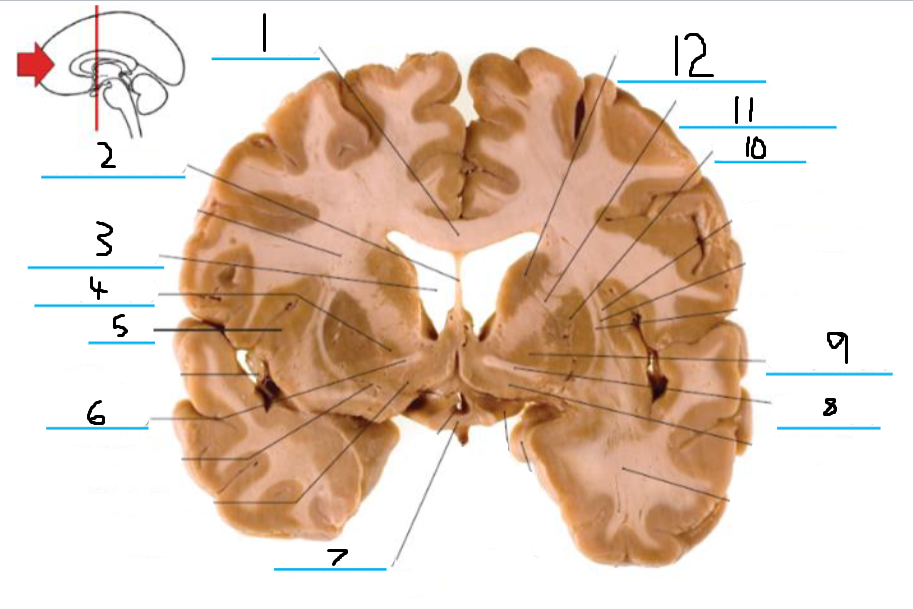

#1 is the:

Corpus Callosum

#2 is the:

Lateral Ventricle

#3 is the:

Septum Pellucidum

#4 is the:

#5 is the:

Insula

#6 is the:

Cingulate Gyrus

#7 is the:

Caudate

#8 is the:

Internal Capsule

#9 is the:

Putamen